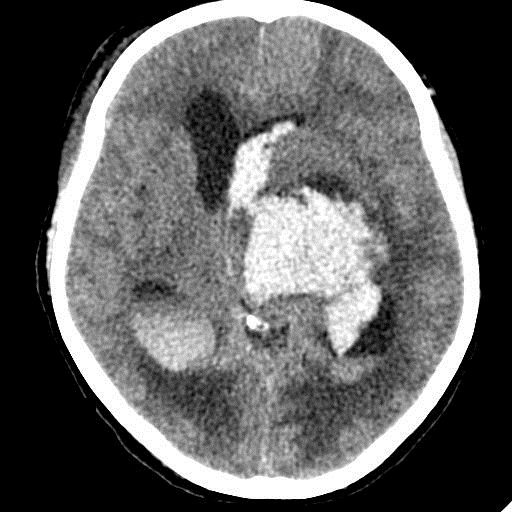

Острое внутримозговое кровоизлияние с выходом крови в желудочки (боковые - сгустки преимущественно в левом + эффект седиментации с горизонтальным уровнем жидкость\жидкость в задних рогах; сгустки крови в третьем желудочке, кровь в четвертом). Значительное увеличение височных рогов боковых желудочков - гидроцефалия. Смешение срединных структур вправо, отек белого вещества перивентрикулярно слева.

Я написала отек мозга, острое массивное (около 100 мл только внутримозговое) смешанное кровоизлияние слева + в стволе, с прорывом и гемотампонадой желудочков, выраженной латеральной дислокацией (13 мм), менингиома? лобного полюса слева. Убедительных данных за опухоль, давшую кровоизлияние, не вижу, хотя такая мысль тоже была.  Контрастировать такую пациентку никто не будет, агонизирующая(.

Тоже за менингиому, т.к. вижу широкое прилежание к серпу, неровные но четкие края образования и явное отграничение от ткани мозга, единичные кальцинаты, отсутствие воздействия на лобную кость.

У, сколько всего написано. Пока не пришла Nela, поучаствую и я. 1. Кровоизлияние в ткань мозга, а не в опухоль: а)не видно ткани опухоли; б) неясна первичная локализация опухоли (левые базальные ядра?!); в)нет перифокального отека вокруг предролагаемой опухоли, г) при опухолях прорывы в желудочки - редкость; 2) к поперечной дислокации добавил бы безесловную аксиальную: даже цистерна моста сужена, не говоря уже про обходную-четверохолмную и другие; 3) менингиома в левой лобной области, на мой взгляд, сомнительна (кстати, покажите ее пожалуйста), ИМХО - "игра" плотностей;  4) ///метастазы в сосудистые сплетения/// - это очень круто, но они не дали бы внутримозгового кровоизлияния, как и ///плексуспапилома///.

Массивное медиальное кровоизлияние с прорывом в желудочки. Кровоизлияние в ствол. Признаки вклинения. В лбу может что-то и есть, но это не принципиально. А может быть и отечные извилины. Смущает, что нет масс-эффекта.

Совершенно согласна, что есть и аксиальная дислокация, и что нечто в лобной - не принципиально, но есть).